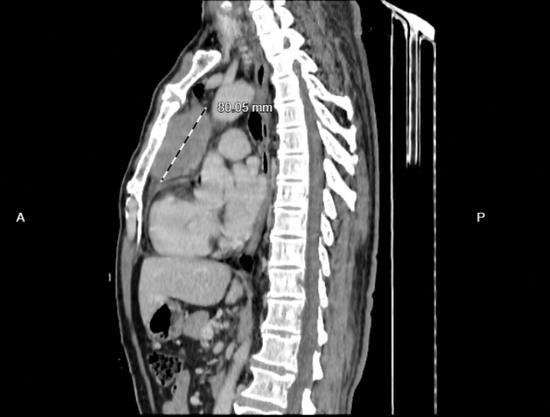

影像检查结果令人揪心:一个尺寸约7*8cm的巨大肿块,盘踞在紧邻心脏的前上纵隔区域。这颗肿瘤位置极其险要,不仅严重压迫周围组织,更已侵犯心包,如同一颗“不定时炸弹”,随时可能影响心脏功能,危及生命。

▲纵隔肿瘤CT